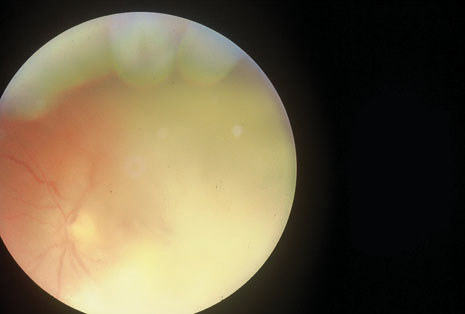

Many forms of uveitis are characterized by specific types of inflammatory cells. Usually, however, one encounters mixtures of cell types in any given specimen, with the relative percentages of lymphocytes and polymorphonuclear leukocytes varying. There may be unusual numbers of eosinophils, or macrophages laden with lens material may be present. Thus, an enumeration of the cells and a careful analysis of their structure can be useful as a diagnostic aid (Figs. 7, 8, 9, 10, 11, 12, 13, 14, 15, 16, 17, 18, 19, and 20). Figure 15 demonstrates eosinophils that were aspirated from the anterior chamber of a patient with Toxocara canis endophthalmitis. Figure 12 demonstrates malignant cell infiltrate from the vitreous, showing the stained presence of monoclonal light chains being elaborated in the cytoplasm. Interleukin-10, detectable in the vitreous of intraocular lymphoma patients, is also directly indicative of both the clinical activity and the number of malignant cells as observed by cytopathology.

Precise identification and culture of bacterial and fungal pathogens from both the aqueous humor and the vitreous fluid can be obtained. Gram's stain and Giemsa's stain smears of centrifuged specimens from the aqueous humor and the vitreous humor frequently demonstrate the bacterial or fungal causative agent. Attempts to isolate bacteria and fungi and to identify them on Gram's stain or Giemsa's stain smears have been most rewarding in the following cases: (a) postoperative endophthalmitis, (b) infection after a penetrating injury of the eye, (c) drug abuse patients with endogenous endophthalmitis (Figs. 21, 22, 23, 24, and 25), (d) patients receiving hyperalimentation, and (4) patients who are immunocompromised as a result of exogenous immunosuppressive agents.

Studies have demonstrated the usefulness of ocular paracentesis for the identification of ocular infections in order to implement sight-saving treatment.10–16 Even acid-fast bacilli and viruses may be diagnosed in this fashion when emergency dictates (see Fig. 5).17 It is recommended that diagnostic paracentesis be performed in all cases of postoperative endophthalmitis, and it is safe to perform the postoperative procedure in the operating room with the safety of vitrectomy surgery. Further, any patient older than 65 who presents with a deteriorating uveitis (usually with vitreitis as the predominant infiltrate) of undetermined etiology should undergo paracentesis of the vitreous to rule out reticulum cell sarcoma (large cell lymphoma).18 Similarly, any patient suspected of being an intravenous drug abuser who presents with an endogenous endophthalmitis or uveitis should undergo diagnostic paracentesis to avoid allowing an intraocular infection to be borne by the bloodstream.19,20